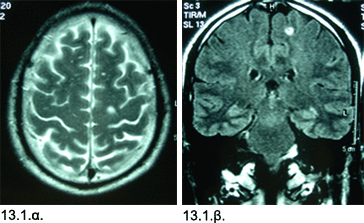

Εικόνες 13.3.α. & 13.3.β. Μαγνητική τομογραφία αναδεικνύει την μικρή ζώνη επιληπτογόνου ιστού (ως σκουρόχρωμη τριγωνική περιοχή) που αφαιρέθηκε στην δεξιά έσω μετωπιαία χώρα, προσφέροντας έλεγχο των επιληπτικών κρίσεων, σε στεφανιαία (13.3.α.) και εγκάρσια προβολή (13.3.β.).

Επεμβατική αντιμετώπιση: Με βάση τα παραπάνω ευρήματα, έγινε ψηφιακά κατευθυνόμενη εκτομή της δεξιάς έσω μετωπιαίας έλικας και διατομή του προσθίου 1/3 των ινών του μεσολοβίου

Έκβαση: Ο πάσχων υπέστη αρκετές μετεγχειρητικές εστιακές κρίσεις τις πρώτες 8 ημέρες, και παρουσίασε αρχικά προσωρινή υπερθυμία και βουλιμία,

αλλά βελτιώθηκε σε μικρό διάστημα και έκτοτε παρέμεινε χωρίς νευρολογικό έλλειμμα και ελεύθερος επιληπτικών κρίσεων.